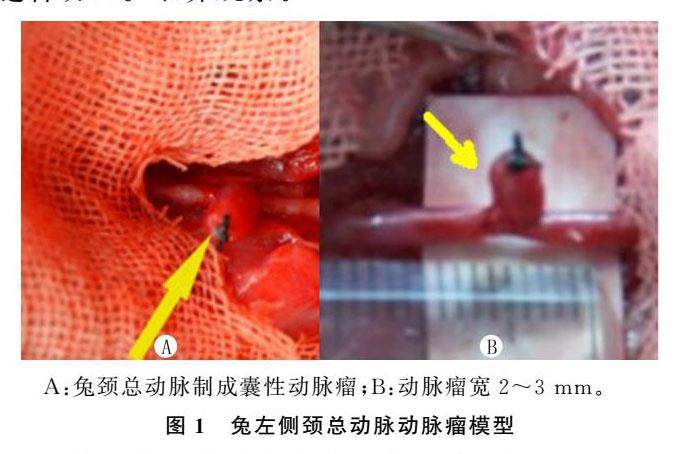

论著 | 紫归长皮软膏上清液涂层可脱电解弹簧圈栓塞囊性动脉瘤效果

论著 | 紫归长皮软膏上清液涂层可脱电解弹簧圈栓塞囊性动脉瘤效果